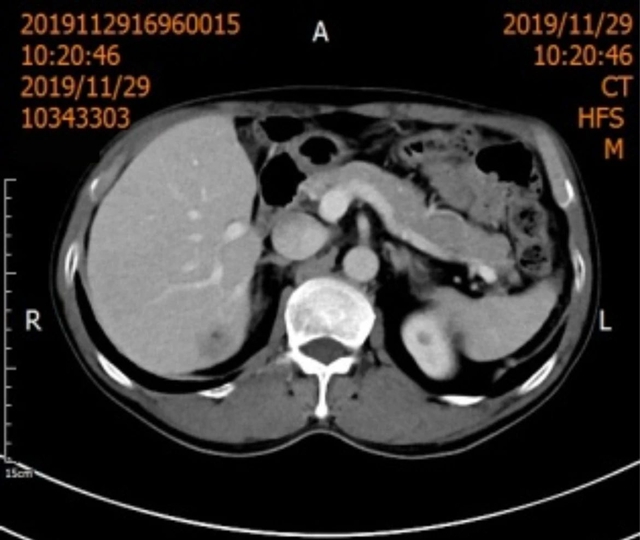

2019年12月3日,66岁的吴先生因“两对半异常10余年,发现肝占位1天”到西南医科大学附属中医医院就诊。

肝胆病科副主任王晓栋副教授接诊后为其完善相关检查后,结果提示:甲胎蛋白17.18ng/ml;腹部CT:肝硬化,肝右后叶低密度影;腹部MR:肝硬化,肝右叶后下段结节灶,考虑肝癌可能性大。

综合吴先生的病史资料,临床诊断为肝癌,根据影像学表现,王晓栋副教授建议吴先生可行手术切除或微创消融治疗,吴先生及家属考虑到年龄、糖尿病等因素,最终决定行“经皮肝脏肿物冷冻消融术”。